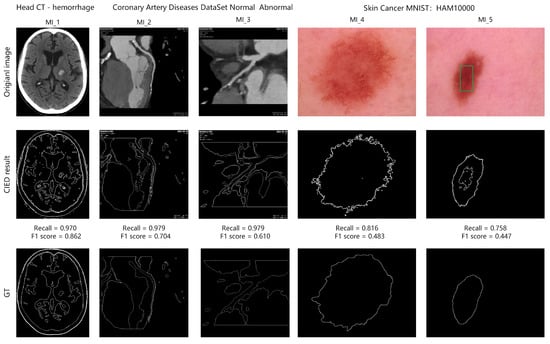

To evaluate the intuitive visual effort, we use the CIED method for edge detection on medical images. Partial results are shown in Figure 5. The first row MI_1 to MI_5 is the original medical images, the second row is the detected edge images of CIED, and the third row is the GT of the medical images. In addition, Figure 5 also shows the recall and F1-score of the edge detection results. We can intuitively observe that CIED can extract complete and clear edges stably even though these images come from different types and have different contrast distributions. From the detection results of MI_1 in Figure 5, the CIED can extract the boundary of different tissues and structures of the brain completely. From the detection results of MI_2 and MI_3 in Figure 5, CIED can extract the complete heart contour and can accurately detect the contour edges of the coronary arteries. As a result of MI_4 and MI_5 in Figure 5, CIED can accurately extract the edges of skin lesions and meanwhile capture their subtle features. For example, as shown in the results of MI_5 in Figure 5, the detected edge in the green box further targets the core lesion area. In addition, recall is high in all edge detection results, indicating that CIED has a high edge detection rate. Overall, in terms of visual effect, CIED can not only effectively extract the key contours in medical images, but also extract the edges with slight variations, and these edges can further help doctors target the potential lesion areas.

Figure 5.

The demonstration of detected edge images using proposed CIED in different images. The green box indicates the potential edges of the skin lesion.